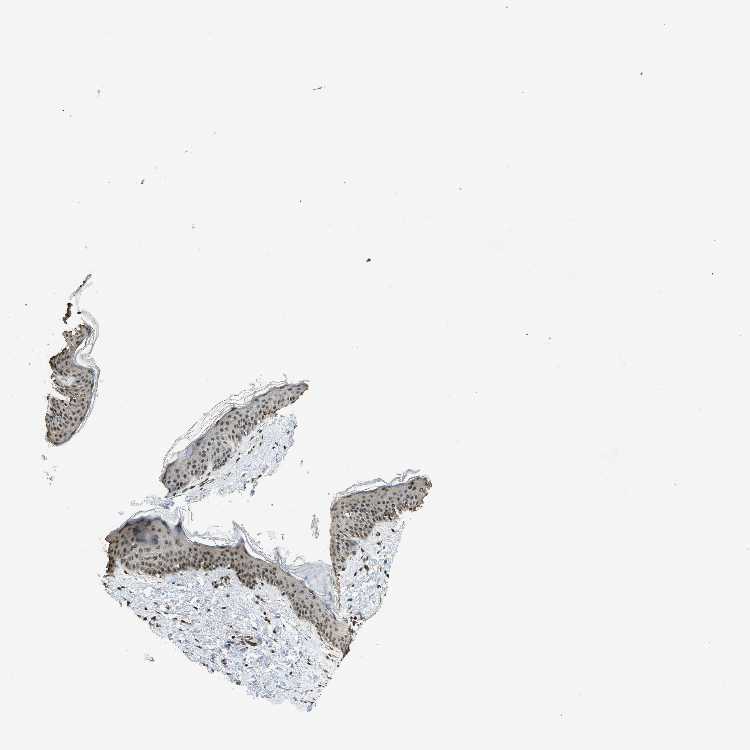

SKIN 1 - Antibody stainingi

Antibody staining in the annotated cell types in the current human tissue is reported as not detected, low, medium, or high, based on conventional immunohistochemistry profiling in selected tissues. This score is based on the combination of the staining intensity and fraction of stained cells.

Each image is clickable and will lead to virtual microscopy that enables deeper exploration of all samples and also displays staining intensity scores, fraction scores and subcellular localization as well as patient and tissue information for each sample.

Antibody CAB017704

Langerhans Medium

Fibroblasts Medium

Keratinocytes Medium

Melanocytes Medium